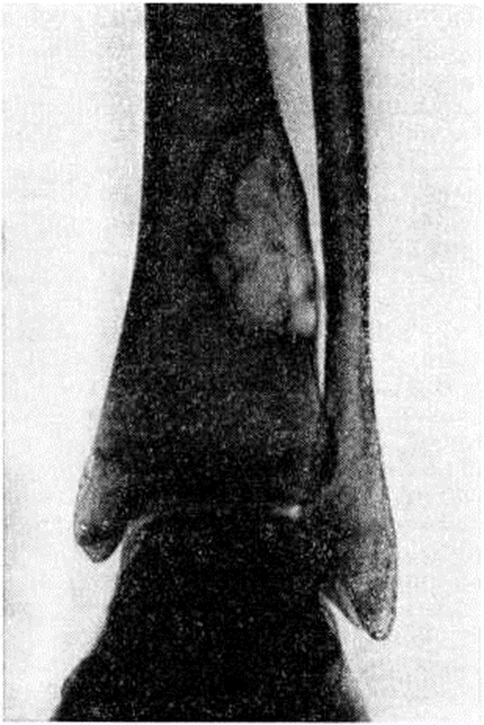

При очаговой форме Фиброзная остеодисплазия обнаруживают участки ограниченного просветления костной ткани, располагающиеся эксцентрически в области коркового (компактного) вещества кости. Первоначально возникающие узлы чётко отграничены друг от друга скорлупообразной уплотнённой полоской костной ткани. По мере развития заболевания размеры очагов увеличиваются; обнаруживается истончение коркового вещества, которое приобретает неровные серповидные или фестончатые очертания. Кость как бы вздувается изнутри, становится бугристой. Иногда выявляют одновременно несколько изолированных очагов Фиброзная остеодисплазия, которые нечётко отграничены друг от друга, но все же сохраняют относительную самостоятельность; при этом кость приобретает крупноячеистый вид (рисунок 3). Корковое вещество её резко истончается за счёт эндостальной резорбции. Поперечник кости на значительном протяжении неравномерно утолщается. В некоторых случаях очаги Фиброзная остеодисплазия определяются в виде отдельных гнездных образований, разбросанных по длиннику кости среди неизменённой или малоизменённой, в основном склерозированной, костной ткани. Структура очагов может быть различной. Часто они имеют вид гомогенных просветлений, реже — мелкоячеистую, ноздреватую структуру, иногда содержат отдельные участки уплотнения, обызвествления или окостенения в виде неправильно сформированных костных балок. Локализация, размеры и количество очагов изменяются в процессе роста и развития костно-суставного аппарата; наблюдается тенденция к их слиянию, смещение к середине диафиза. При стабилизации заболевания рентгенологическое картина длительное время сохраняется неизменной.